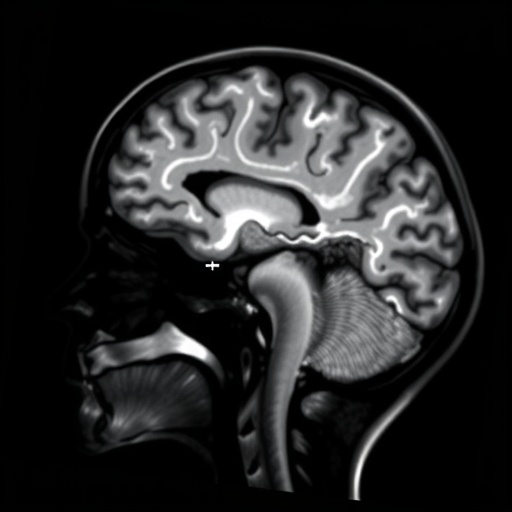

Neonatal encephalopathy, a condition characterized by disturbed neurological function in newborns, often stems from perinatal hypoxic-ischemic injury. Its unpredictable trajectory frequently leaves clinicians grappling with imprecise prognoses, making treatment decisions daunting. Standard MRI metrics, while invaluable, primarily provide averaged diffusion measurements that fail to capture the intricacies of brain tissue heterogeneity. Diffusion kurtosis imaging, by contrast, extends beyond these traditional limits by assessing the degree of non-Gaussian water diffusion, thus illuminating subtler microstructural alterations. These distinctions hold potential to unravel complex pathophysiological processes occurring in the vulnerable neonatal brain.

At the core of DKI’s promise lies its ability to quantify kurtosis parameters, which essentially describe the deviation of water diffusion from simple Gaussian behavior. This sensitivity to microenvironment complexity enables the detection of subtle changes in cellular organization, density, and integrity—particularly relevant in the context of neonatal brain injury characterized by heterogeneous involvement of gray and white matter. Importantly, this could permit earlier and more accurate identification of infants at risk for long-term neurodevelopmental impairments, potentially before conventional imaging signs become evident.

The study in question meticulously explores the application of DKI metrics in neonates with varying severities of encephalopathy, mapping diffusion kurtosis parameters across several brain regions integral to motor, sensory, and cognitive functions. By correlating these diffusion profiles with clinical outcomes, including neurodevelopmental milestones recorded months later, the research aims to establish robust biomarkers that transcend the temporal limitations of current evaluation paradigms. The results reveal a complex interplay between regional kurtosis abnormalities and clinical prognosis, highlighting both the promise and current boundaries of DKI.